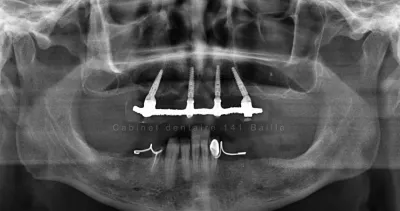

Qu'est ce que la technique all on 4 en implantologie.Cabinet 141 Baille Marseille.

Que veut dire ALL ON 4 ou Quattro en implantologie ?.Quand peut on mettre en oeuvre cette technique.Avantages et inconvénients de cette technique.

La technique On all 4 permet de reconstituer une arcade complète fixée sur 4 implants dentaires.C'est une solution rapide effectuée dans la journée et économique.Le Cabinet du Dr Tourrolier est spécialisé dans ce type de technique.